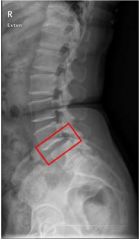

34 60 歲婦女慢性腰痛 2 年,未積極治療,其 X 光如圖所示,下列處置何者適宜?①立即進行手術,腰 椎放鋼板以免惡化 ②適時穿戴護腰 ③患處疼痛可外敷活血止痛藥膏 ④多訓練腰背肌肉、四肢 肌肉 ⑤適度的牽引也可使用 (A)①④⑤ (B)①②③ (C)僅②④⑤ (D)②③④⑤